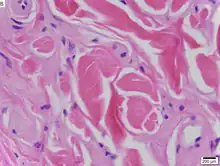

La maladie est causée par des mutations type perte de fonction du gène de la protéine de la matrice extracellulaire 1 (ECM1)[5] localisé sur le chromosome 1 en 1q21. Les symptômes dermatologiques sont causés par l'accumulation d'un matériau hyalin dans le derme et l'épaississement de la membrane basale de la peau[2]. La maladie de Urbach-Wiethe est généralement diagnostiquée par ses manifestations cliniques dermatologiques, en particulier les papules perlées sur les paupières. La découverte des mutations du gène ECM1 a permis l'utilisation de tests génétiques pour confirmer un premier diagnostic clinique. La coloration acide periodique-Schiff (PAS) et l'immunohistochimie peuvent également être utilisées pour le diagnostic[1],[6].